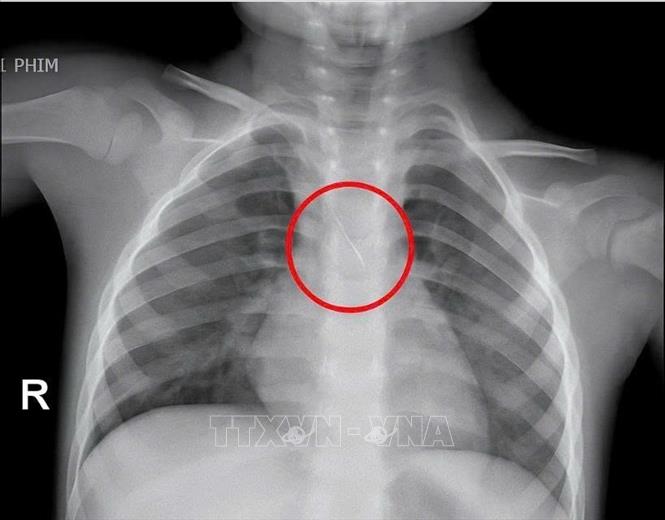

Trước đó, bệnh viện tiếp nhận bé N.Q.T.Đ (3 tuổi), trú tại xã Cửa Việt, Quảng Trị trong tình trạng ho nhiều, ho sặc. Kết quả chụp phim cho thấy, một dị vật kim loại dài khoảng 22mm nằm ở góc carina (vị trí chia đôi khí quản) đe dọa gây tắc nghẽn đường thở của trẻ.

Hình ảnh chiếc kim chọc tuỷ rơi vào trong đường thở của bé trai 3 tuổi. Ảnh: TTXVN phát

Ngay lập tức, các bác sỹ đã hội chẩn liên khoa và quyết định nội soi phế quản cấp cứu. Dị vật được phát hiện có một đầu nhọn cắm vào 1/3 dưới khí quản, đầu còn lại nằm trong phế quản gốc trái, được xác định rất nguy hiểm. Sau 15 phút thao tác khẩn trương, dị vật được kíp mổ lấy ra an toàn. Bé trai cải thiện triệu chứng ngay sau can thiệp và xuất viện sau 48 giờ theo dõi.